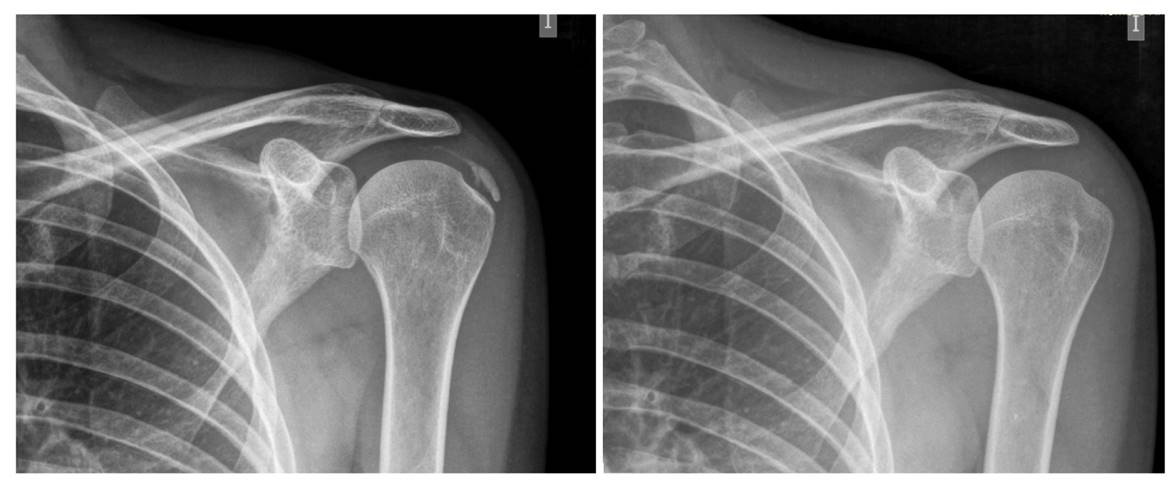

El diagnóstico de confirmación es por una simple radiografía. En la zona del espacio subacromial aparece una calcificación, de mayor o menor tamaño, que no debería aparecer y que forma parte del tendón del supraespinoso más comúnmente (del manguito de los rotadores en general).

El diagnóstico se corrobora por ecografía, prueba dinámica que permite determinar tamaño y forma, espesor y volumen de la calcificación. Nos permite detectar la ubicación exacta de la calcificación y también detectar microcalcificaciones de 1 mm poco valorables en radiografía convencional.